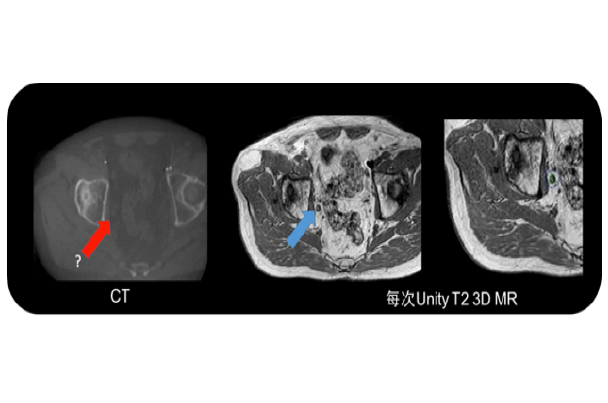

磁共振成像可高精度显示寡转移灶,为靶区精确投照提供影像学定位,开展放射消融治疗。